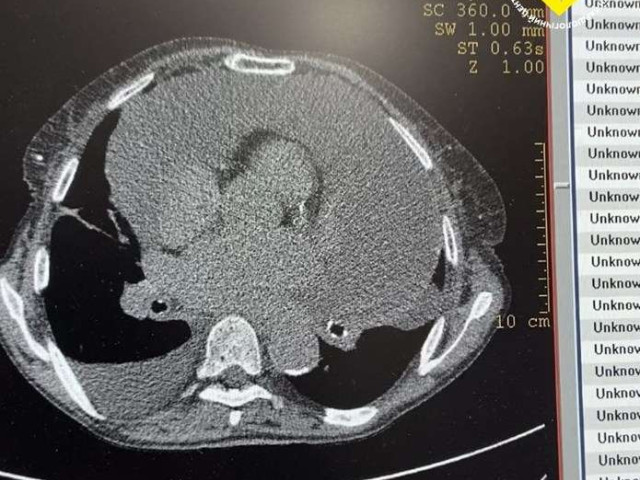

Щоб встановити причину задухи, пацієнтці провели комплексне обстеження: ехокардіографію, рентген та КТ органів грудної клітки. У результаті вдруге підтвердили діагноз гідроперикардиту - скупчення надлишкової рідини в перикарді, пише МА АСС з посиланням на фейсбук-сторінку медзакладу.

Під час втручання з порожнини перикарда видалили 2 літри 400 мл рідини. Після цього стан жінки значно покращився. Для контролю її здоров’я медики повторно провели ехокардіографію та комп’ютерну томографію, щоб оцінити стан перикарда та з’ясувати причину виникнення небезпечної ситуації.